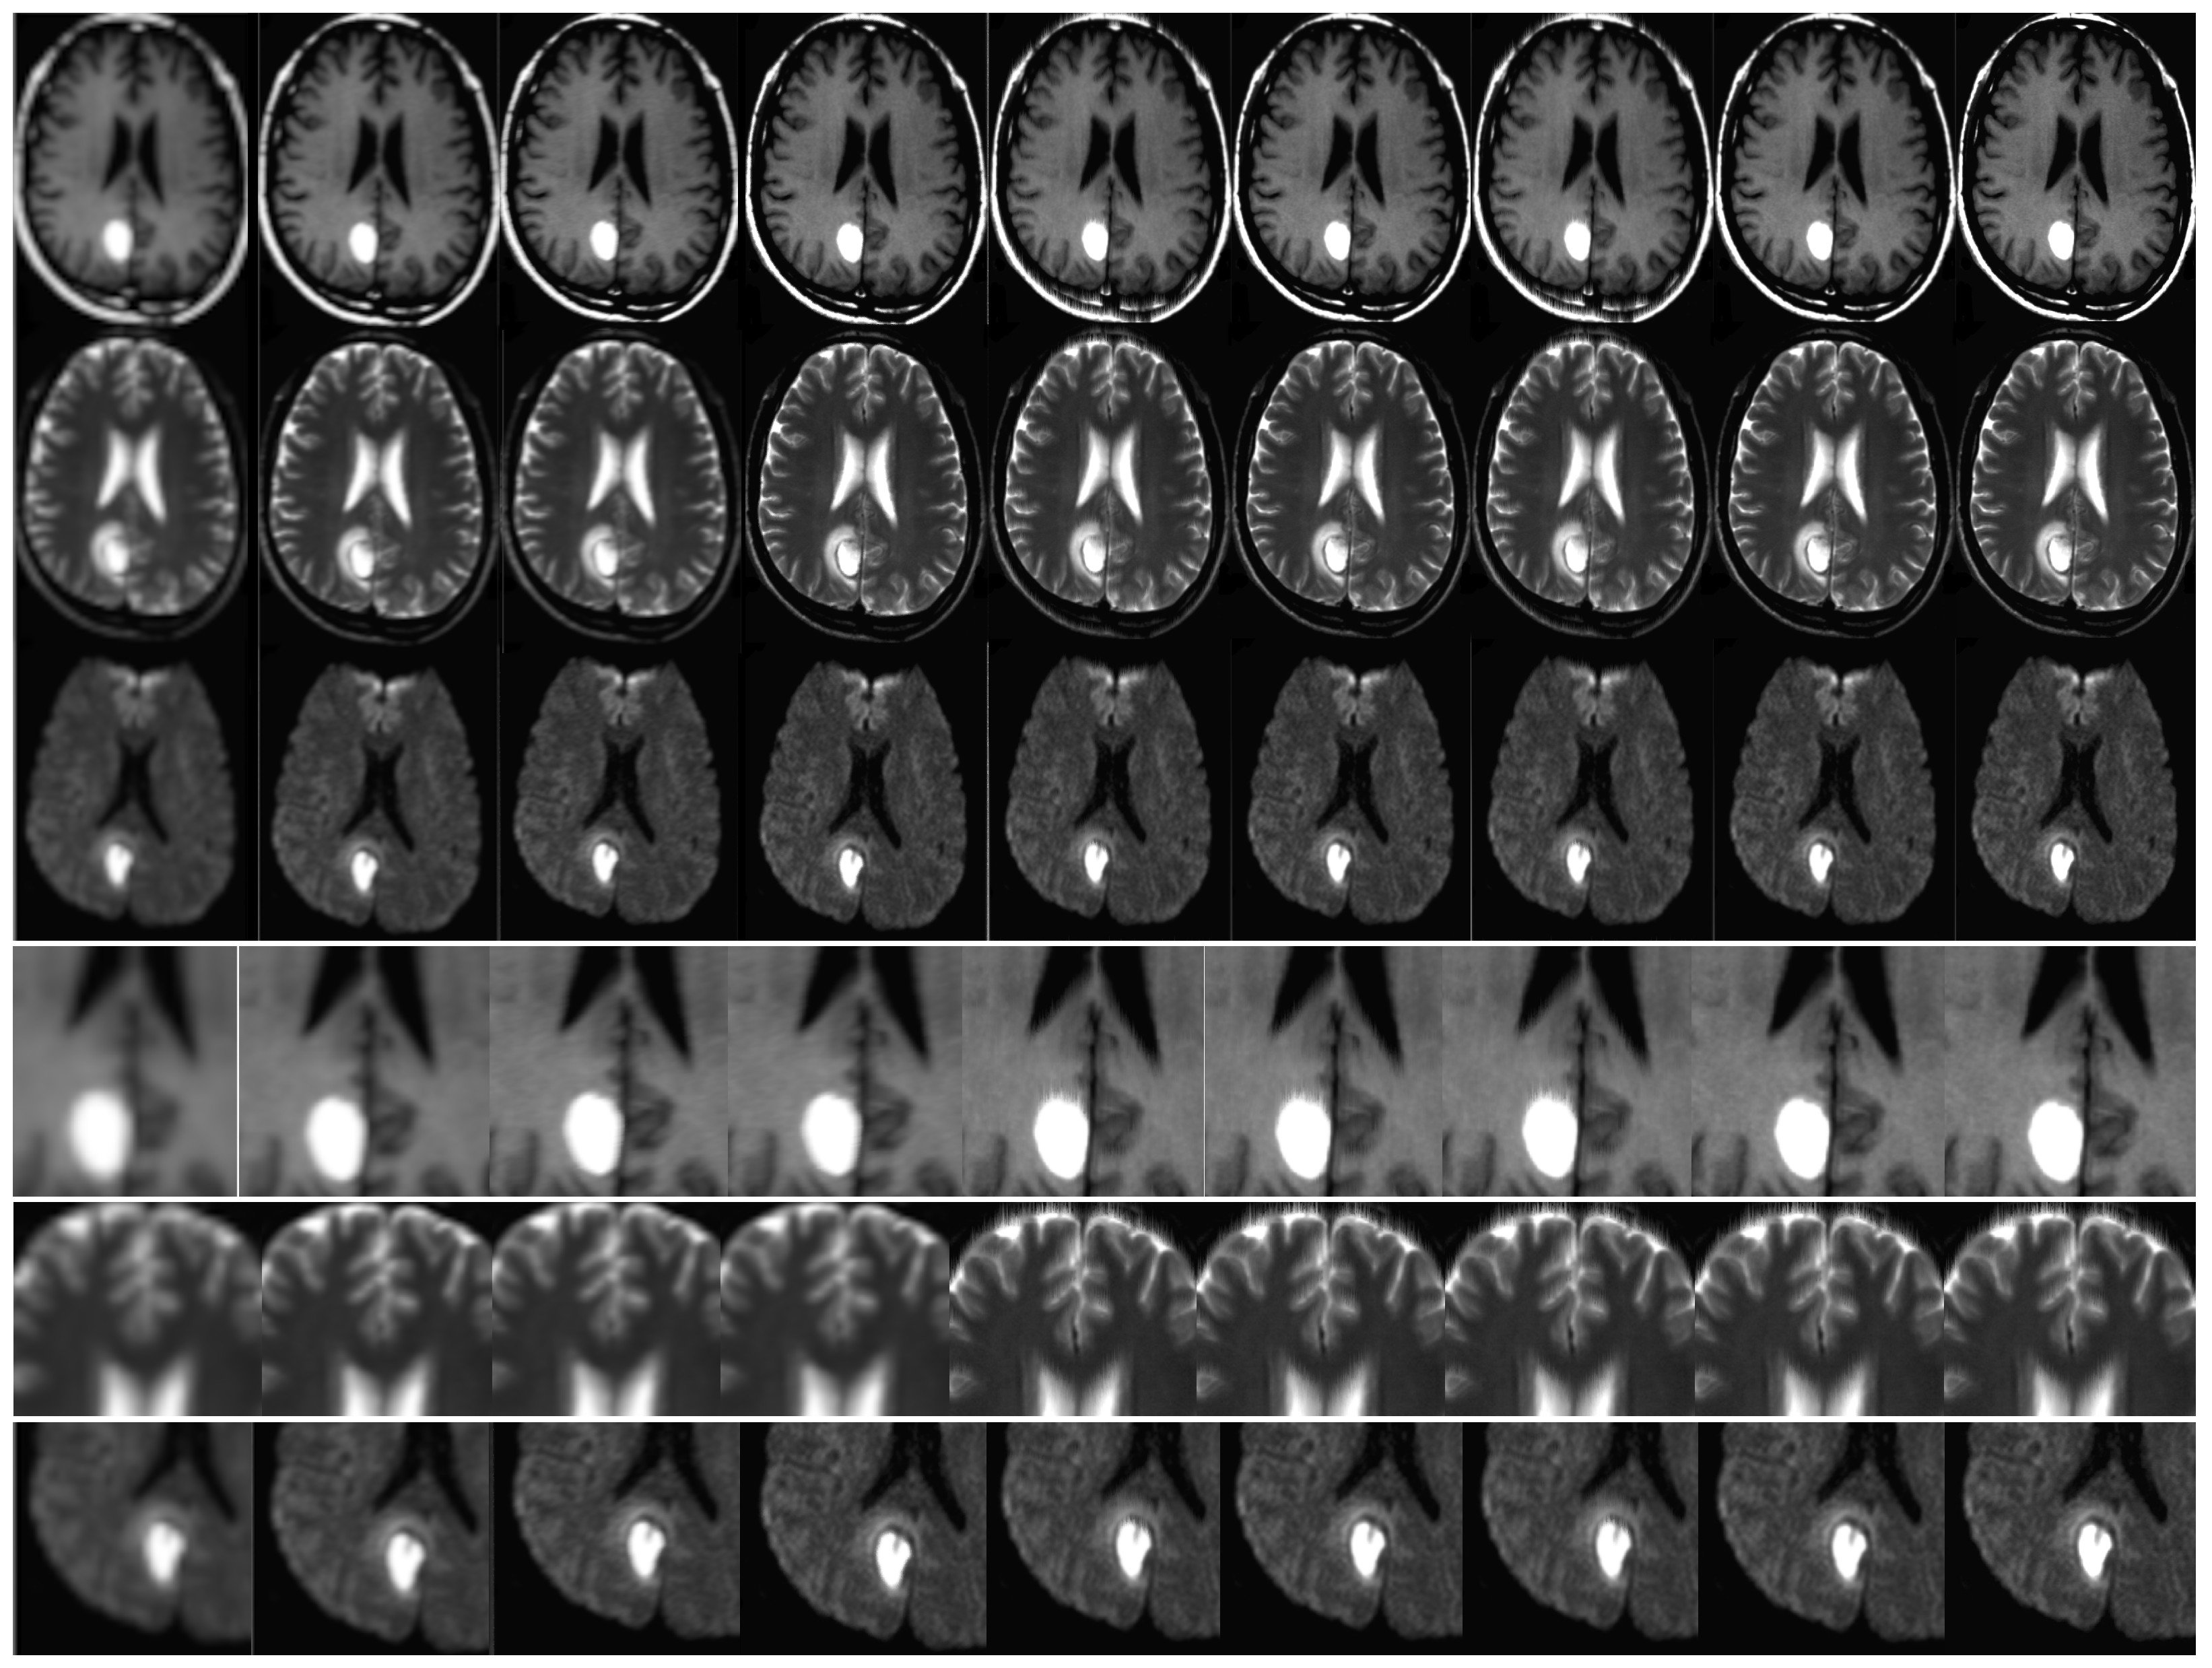

The effectiveness of the algorithm was assessed through the analysis of in vivo patient cases and phantom data. The MATLAB software was utilized for conducting all trials and investigations. The objective of the assessments was to assess the effectiveness of super-resolution image reconstruction through the utilization of compressed input. An additional aim was to assess the efficacy of the MR sampling technique. This study involved the analysis of both in vivo and phantom data. The simulation results are illustrated in Figure 8 and Figure 9. It is noteworthy that the utilization of Compressed Sensing in conjunction with its conjugate symmetry and partial Fourier technique expedites the process of data acquisition in comparison to alternative unaltered k-space sampling patterns. The analysis of human data involved the processing of Siemens Prisma scanner files, which had a measurement of 3.0 terabytes. In order to replicate the performance of a multi-channel head coil across a range of in-plane resolutions, diffusion directions, and slice thicknesses, fully sampled k-q spaces have undergone decimation. The denoising problem is defined within the framework of Maximum A Posteriori (MAP) estimation by the proposed method. The algorithm for noise reduction under consideration yields an average value of approximately 2.1 dB, as determined by the tests conducted. Phantom-based experiments were conducted on high-quality DW multi-shot EPI sequences. The simulation of off-resonance effects was conducted utilizing fugue. The study employed D-BRAIN phantom models, which are diffusion MRI brain data models that are anatomically precise. The training of the model was conducted on an NVIDIA DGX machine equipped with GPU A100, utilizing the resources of Google Colab Pro. The generator undergoes training using a pair of LR images, which are stacked and have dimensions of 60 × 60 × 2. The objective is to generate a single HR image with dimensions of 240 × 240. The generator employs a tripartite loss function comprising of content loss, perceptual loss, and adversarial loss. The discriminator is subjected to both the SR and HR images obtained from MRI. The binary classifier known as the discriminator employs binary cross-entropy as its optimization technique. The utilized optimizer is Adam, which is applied to both the generator and discriminator. The learning rate is 10 5 (Table 1, Table 2, Table 3, Table 4 and Table 5).

Please refer to Figure 7 and Figure 8 for empirical support of the enhancement in both image resolution and quality. The improved resolution and legibility of the procedures utilized for potentially malignant or premalignant lesions have resulted in an increased capacity to detect them. The method’s anticipated efficacy is largely attributed to its potential advantages, such as achieving a heightened contrast while preserving a superior level of resolution. The present study investigates the integration of magnetic resonance (MR) with super-resolution and compressed-sensing techniques. The enhancements that were obtained have led to notable improvements in sharpness, edge interpretation, and contrast. The achievements have been verified by PSNR as well. The impact of CS quality ratios on PSNR values is significant, as demonstrated by the Table 1, Table 2, Table 3, Table 4 and Table 5.

The average peak signal-to-noise ratio (PSNR) is computed by utilizing various method outputs and ground truth images. The simulation was conducted on one hundred occasions. To ensure the statistical reliability of quality measurements, the PSNR calculation procedure was replicated for every simulation case and subsequently averaged. It is noteworthy that the most favorable outcomes were achieved utilizing a compression ratio of 50%. This implies that a further reduction in the overall quantity of input samples leads to a slight improvement in the peak signal-to-noise ratio (PSNR), as evidenced by the data presented in Table 1, Table 2, Table 3, Table 4 and Table 5. The reduction in exam duration is directly proportional to this particular value. Furthermore, this approach has the potential to mitigate motion distortions in addition to compromising on resolution. The approach centers on expediting the convergence of algorithms, incorporating image prior, and recognizing blur kernels. Preliminary trial data can serve as valuable background information to expedite the duration of examinations. Notwithstanding the capability of the motion estimation algorithm to significantly mitigate diagnostic image artifacts, thereby enhancing the probability of an accurate diagnosis; it is incapable of completely eliminating all artifacts. Figure 8 and Figure 9 demonstrate an enhancement in the resolution and caliber of the outcomes acquired. The results mentioned above are provisional and susceptible to modification. The algorithm’s advantages were demonstrated through a qualitative evaluation of the neuroimages of twenty patients. The study involved the collection of DW-MRI data from twenty patients with oncological conditions, using a single scanner. The calculation of the mean square error (MSE) was performed for each instance of reconstruction in order to obtain statistically significant measurements. The study employed the signed rank test to examine the null hypothesis that the central tendency of the difference across different sparsity rates was equivalent to zero. The statistical analyses were conducted using the R Project for Statistical Computing. A statistical analysis was performed utilizing a t-test for independent groups to compare the mean values of peak signal-to-noise ratio (PSNR) between two distinct groups. Additionally, a paired t-test was conducted to analyze paired data. The algorithm’s robustness has been confirmed by the probability, which was determined through a significance test and Student’s t-test conducted on the PSNR. The outcomes are exhibited in Table 3, Table 4 and Table 5. The statistical significance of the results was high, as indicated by the obtained p-values.